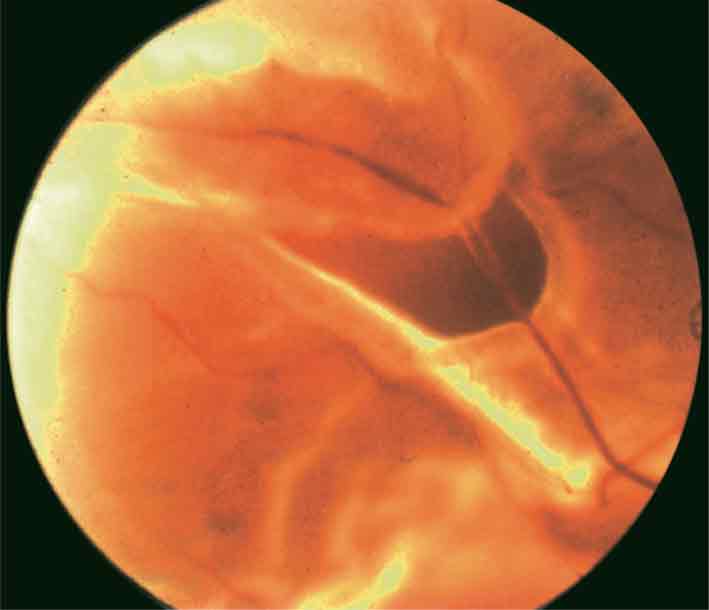

الشكل (6): انفصال شبكية شدي عند مصاب باعتلال شبكية سكري.

يأخذ انفصال الشبكية الشدي شكلاً مقعراً ذا سطح أملس مع انخفاض شديد في حركية الشبكية (الشكل 6).